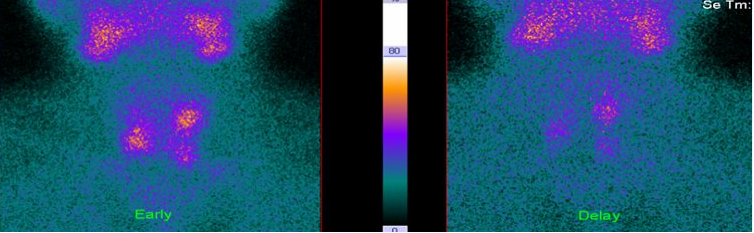

功能正常的甲状旁腺不显影。双时相显像仅见甲状腺显影,颈部无异常浓聚灶;甲状旁腺功能亢进或组织增生时可见病变处显像剂分布异常浓聚。(见图2)

图2 甲状旁腺双时相显像阴性